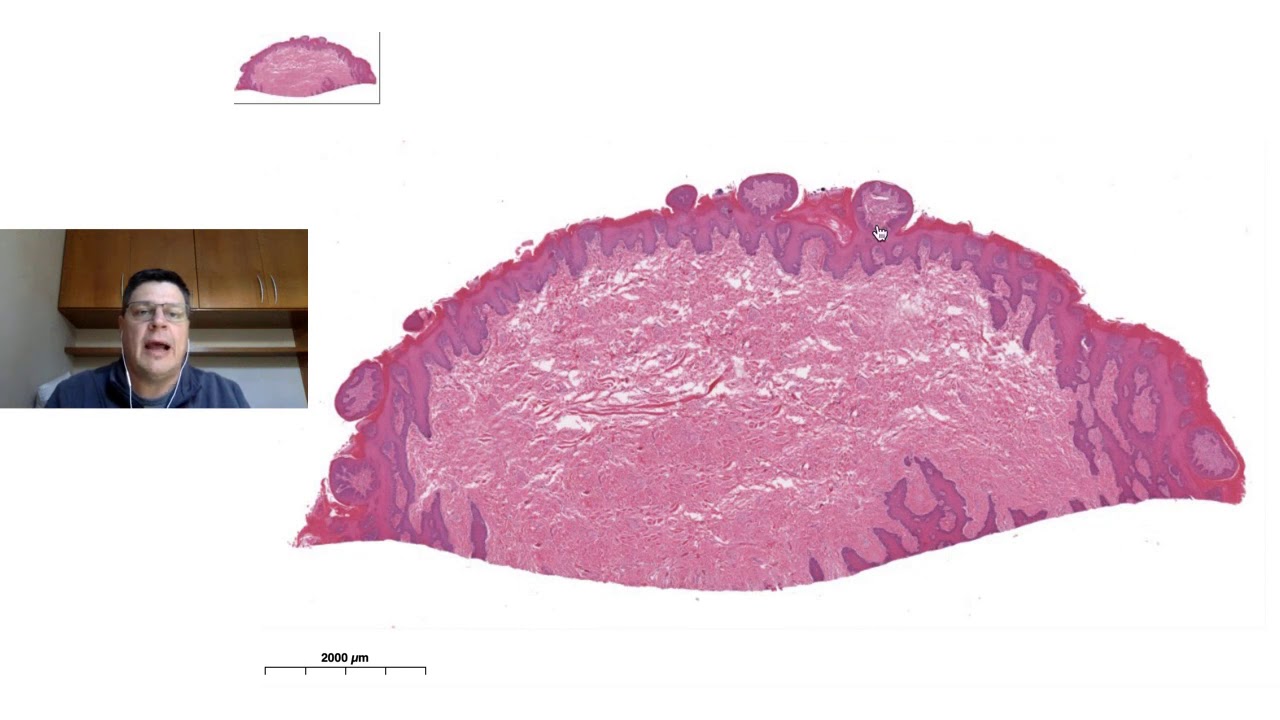

porém lógico que na no septos nós temos fibras colar bom sobre fígado era isso vimos homem de uma maneira geral a e a histologia do fígado e agora nós vamos falar de vesícula biliar a vesícula biliar é um órgão oco que tem como função armazenar e concentrar Billy então o que que acontece no momento em que nós estamos nos alimentando em que tem conteúdo gástrico gastrointestinal a bile é produzida pelo fígado e boa parte vai de cai direto no duodeno nos intervalos entre as refeições na maioria das vezes é sabe não cai no duodeno ela

R ela é conduzida para dentro da vesícula biliar Então por ser um órgão ou com ela tem mucosa submucosa lâmina própria submucosa muscular e serosa ela vai ter uma serosa na borda livre vai ter um Adventista quando tiver em contato direto com fígado a mucosa então quando a gente olha mais de perto a gente vê que ela é cheia de dobras E essas o dobras elas são resultado da vesícula está vazia então por isso que aparece isso a lâmina epitelial dessa mucosa é formada por epitélio cilíndrico Simples então esse epitélio responsável por manter a Bíblia

e e concentrar Billy a lâmina própria é de tecido conjuntivo frouxo como vocês vem aqui nós temos a túnica muscular composta por músculo liso então aqui células com núcleo em formato de charuto músculo liso que é essa a contração desse músculo liso é controlada em grande parte pelos entre hormônios produzidos pelas células enteroendócrinas do estômago e do intestino e por fora nós temos uma serosa nessa nessa porção do corte que a tecido conjuntivo frouxo revestido por epitélio plano simples Então isso é uma a Rosa pro finalizarmos Então nós vamos falar de pâncreas Lembrando que o